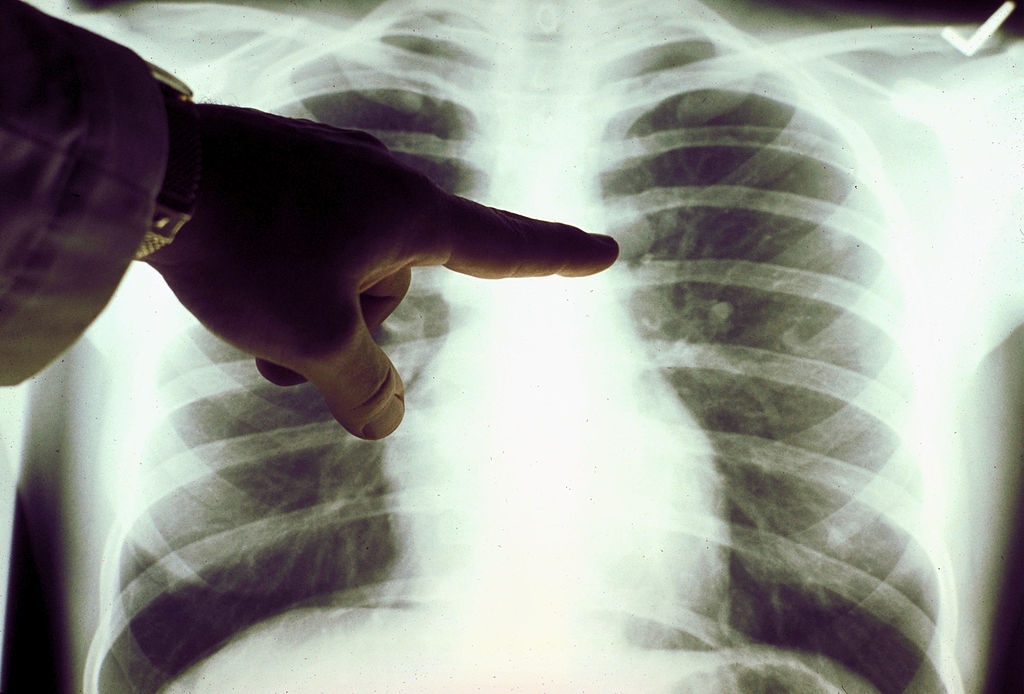

近年來,中國女性肺癌問題日益受到關注。官方數據顯示,從死亡率來看,肺癌已成為中國女性癌症死亡的首位原因,對女性健康構成主要威脅。

據《中國婦女報》報道,提起肺癌,人們往往聯想到男性、吸煙、中老年群體。但近年來,流行病學數據正顛覆這一傳統認知,2024年國家癌症中心發布的《2022年中國惡性腫瘤疾病流行情況分析》顯示——肺癌正在超越乳腺癌,成為中國女性第一大癌種。

數據顯示,女性患者在整個手術人群中的比例不斷上升,從2005年的32%增加到2021年的48%。更值得注意的是,這些女性患者中有超過70%從未吸煙,而男性患者中同類比例不足10%。病理分析進一步表明,女性病例中腺癌的佔比由早期的約60%增加至80%以上。